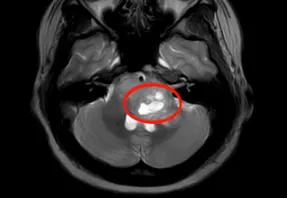

正值青春年华的钱女士,某天突然发现视力模糊,配了光学镜片后视力确实有所改善。尽管如此,她还是决定到医院做进一步检查,结果意外发现中脑背侧存在一枚小结节,大小为1.0×0.6×0.8厘米,影像上考虑低级别胶质瘤可能。

小小结节,低级别胶质瘤?为了搞清楚自己的病情,钱女士辗转多家医院就诊,得到的建议均是暂不干预、密切随访。然而,在接受脑枕部"艾灸"加热治疗后,她出现了持续性头部胀痛,同时伴有恶心及喷射性呕吐。短短两个月内,症状持续加剧——眼睑下垂、向上看困难、持续头痛接连出现。为了进一步明确这枚占位的性质,钱女士接受了头部PET-MR检查,结果提示中脑顶盖小结节,FDG摄取升高,仍考虑低级别胶质瘤可能性大。

02 巴特朗菲教授:没有任何诊断工具能回答"这个病灶究竟是什么"

从核磁及所有检查结果来看,病灶为低级别胶质瘤、处于早期发展阶段,似乎已经相当明确。但巴特朗菲教授指出,仅凭核磁判断胶质瘤类型是远远不够的。无论核磁共振、磁共振波谱拍得多么清晰,还是加做了PET检查,都没有人能够准确判断肿瘤在神经病理学层面的具体类型,尤其无法确定病变的遗传特征。如果这是毛细胞型星形细胞瘤,他不会感到意外;如果是另一种胶质瘤类型,他同样不会惊讶;甚至神经节胶质瘤也不能完全排除,尽管概率相对较小。当然,他认为病变不太可能是炎症,也不倾向于毒性或代谢性病变,因为病灶与正常脑干组织之间的边界清晰。他不建议补充任何额外检查来确定病变类型,因为目前并不存在能够回答"这个病灶究竟是什么"这一问题的诊断工具。